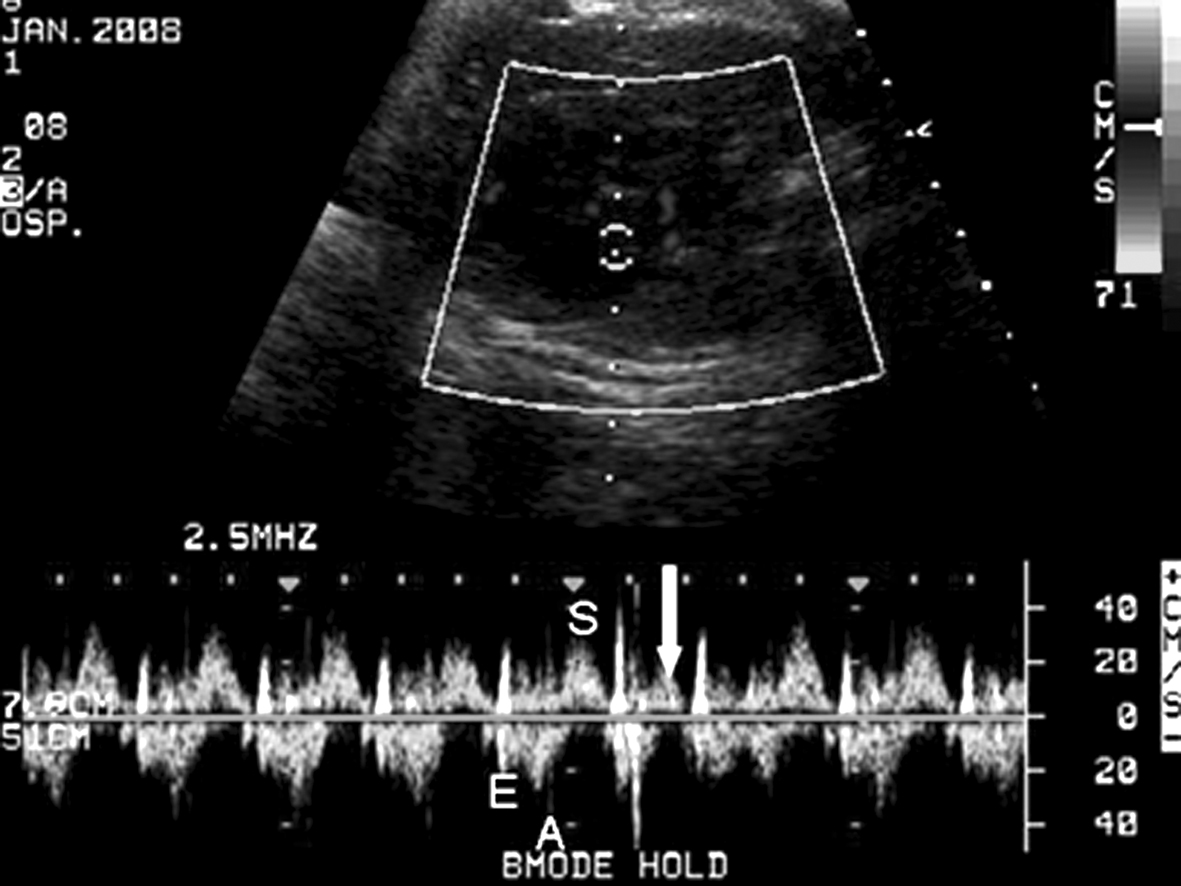

1.将取样门置于左室流入道和流出道交汇处,同时记录心室舒张期的二尖瓣(左室流入道)血流时间流速曲线和收缩期的左室流出道血流时间流速曲线,二尖瓣血流的A峰可反映心房的收缩期(图1)。此多普勒时间流速曲线关系反映了心房心室收缩的依从关系,当出现期前收缩或房室传导阻滞时,该依从关系发生改变。

图1 左室流入道、流出道血流时间流速曲线:E峰、A峰代表心脏舒张期,S峰代表心脏收缩期